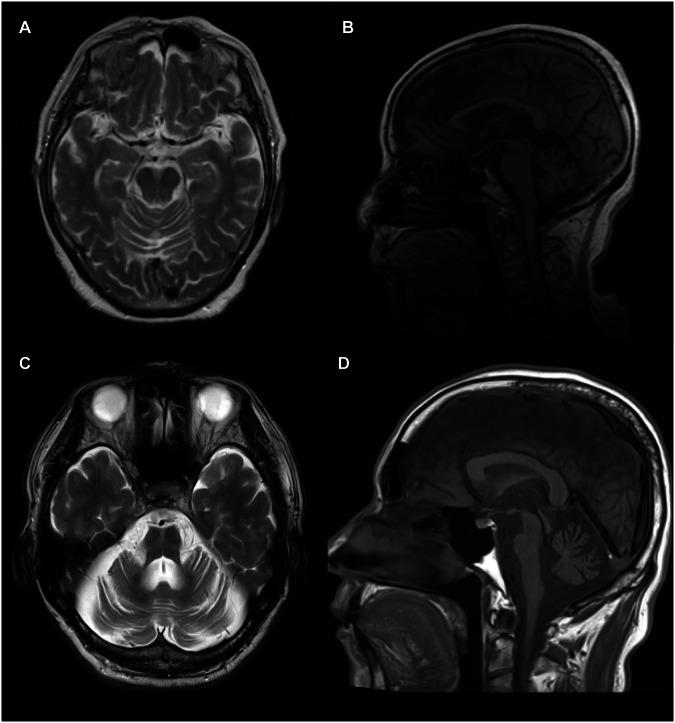

Multiple system atrophy (MSA) is a neurodegenerative disorder characterized by autonomic nervous system dysfunction and cerebellar ataxia or parkinsonism. Recently, expanded GAA repeats (≥250 repeat units) in intron 1 of FGF14 have been shown to be responsible for spinocerebellar ataxia type 27B (SCA27B), a late-onset ataxia with an autosomal dominant inheritance. Patients with SCA27B may also exhibit autonomic nervous system dysfunction, potentially overlapping with the clinical presentations of MSA patients. In this study, to explore the possible involvement of expanded GAA repeats in MSA, we investigated the frequencies of expanded GAA repeats in FGF14 in 548 patients with MSA, 476 patients with undiagnosed ataxia, and 455 healthy individuals. To fully characterize the structures of the expanded GAA repeats, long-range PCR products suggesting the expansion of GAA repeats were further analyzed using a long-read sequencer. Of the 548 Japanese MSA patients, we identified one MSA patient (0.2%) carrying an expanded repeat with (GAA). Among the 476 individuals with undiagnosed ataxia, (GAA) was observed in six (1.3%); this frequency was higher than that in healthy individuals (0.2%). The clinical characteristics of the MSA patient with (GAA) were consistent with those of MSA, but not with SCA27B. Further research is warranted to explore the possibility of the potential association of expanded GAA repeats in FGF14 with MSA.

多系统萎缩(MSA)是一种神经退行性疾病,其特征为自主神经系统功能障碍以及小脑性共济失调或帕金森综合征。最近研究表明,成纤维细胞生长因子14(FGF14)基因内含子1中扩展的GAA重复序列(≥250个重复单元)是导致27B型脊髓小脑共济失调(SCA27B)的原因,SCA27B是一种常染色体显性遗传的迟发性共济失调。SCA27B患者也可能表现出自主神经系统功能障碍,这可能与MSA患者的临床表现重叠。在本研究中,为了探究扩展的GAA重复序列与MSA的可能关联,我们调查了548例MSA患者、476例未确诊的共济失调患者和455名健康个体中FGF14基因扩展的GAA重复序列的频率。为了全面表征扩展的GAA重复序列的结构,我们使用长读长测序仪对提示GAA重复序列扩展的长片段PCR产物进行了进一步分析。在548例日本MSA患者中,我们鉴定出1例(0.2%)携带扩展的(GAA)重复序列的MSA患者。在476例未确诊的共济失调患者中,有6例(1.3%)观察到(GAA);该频率高于健康个体(0.2%)。携带(GAA)的MSA患者的临床特征与MSA一致,但与SCA27B不一致。有必要进行进一步研究,以探索FGF14基因中扩展的GAA重复序列与MSA潜在关联的可能性。